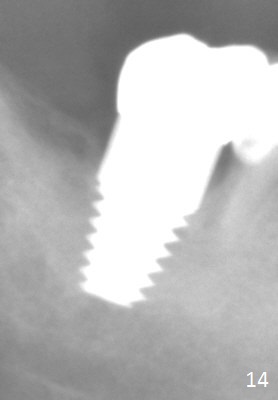

The patient returns for final restoration 5.5 months postop; it appears that the distal gap has disappeared (Fig.13 *). There is no bone loss 26 months post cementation (Fig.14). The lamina dura-like dense bone forms coronally 3 years 4 months post cementation (Fig.15 *). The 8 mm implant remains buried in the bone 5 years 4 months post cementation (Fig.16).